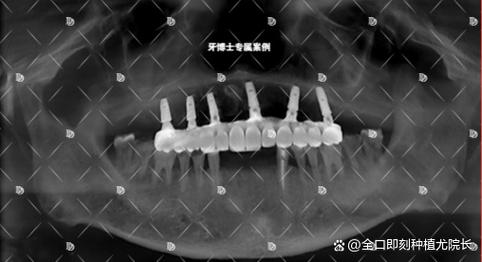

(图片来源网络,侵删) -